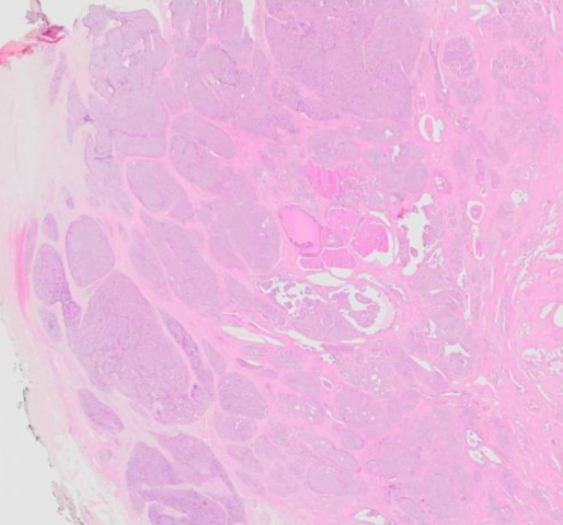

2、数字资源:划分有专门的数字资源模块,包含400多个精细的3D病理虚拟模型、700多个3D病理大体标本、50个手术入路解剖3D模型、400多张病理学数字切片、200多部临床 手术3D动画、30部病理学3D动画、100多部病理学数字切片微视频等资源,以震撼的视觉吸引力、丰富易读的知识点精彩呈现。